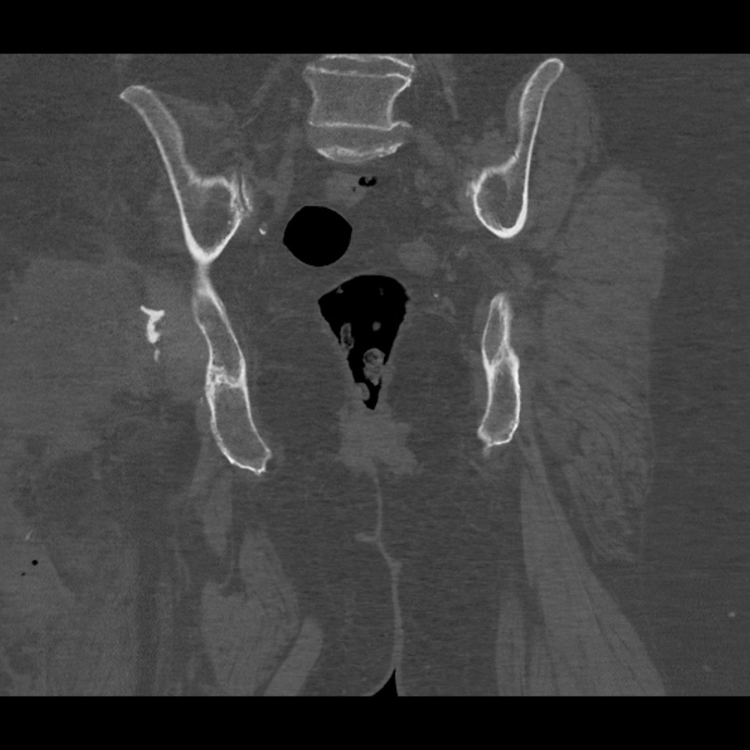

Anteroposterior (AP) radiographs of the patient’s pelvis. The top image shows a located proximal femoral replacement in a custom trial-flange-flange acetabulum.

The bottom image shows that this has dislocated due to instability, causing the patient pain.

Post-Op CT used to design and plan the acetabular component of this revision surgery. It was also used in the planning of the proximal femoral replacement.

This 3D model of the patient’s right hemipelvis has been recreated from the post-operative first stage computer tomography scan demonstrating a Paprosky 3B pelvic defect.